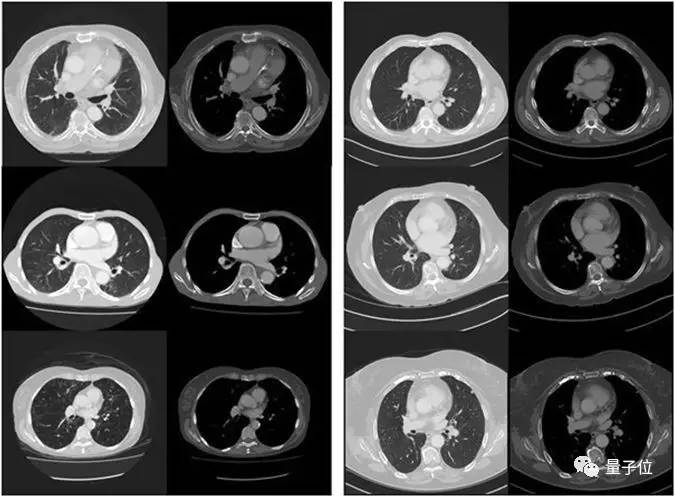

阿德莱德大学公共卫生以及计算机两个学院的研究人员,使用人工智能技术分析了48例患者的胸部医学影像资料,然后预测哪些患者有可能在五年内死亡,准确率达到69%,这与临床医生的“手动”预测不相上下。

虽然研究人员无法准确得知电脑依照什么特征做出的判断,但目前这套系统对预测严重慢性疾病患者的生命周期最有信心,例如肺气肿和充血性心力衰竭。

医学图像的大小,通常比ConvNet能分析的图像大得多。为了降低问题的复杂性,研究人员使用了双三次插值,将大体积的CT数据(512×512像素,每个病例50-70张)下采样为64×64×11的数据。

模型中还添加了七个二进制分割掩码作为信道输入,旨在促进预测任务。通过分割图,每种情况下输入张量的尺寸为64×64×11×8,最终的尺寸不是空间的,而是作为每个像素的“通道”,与彩色照片中的RGB通道相似。